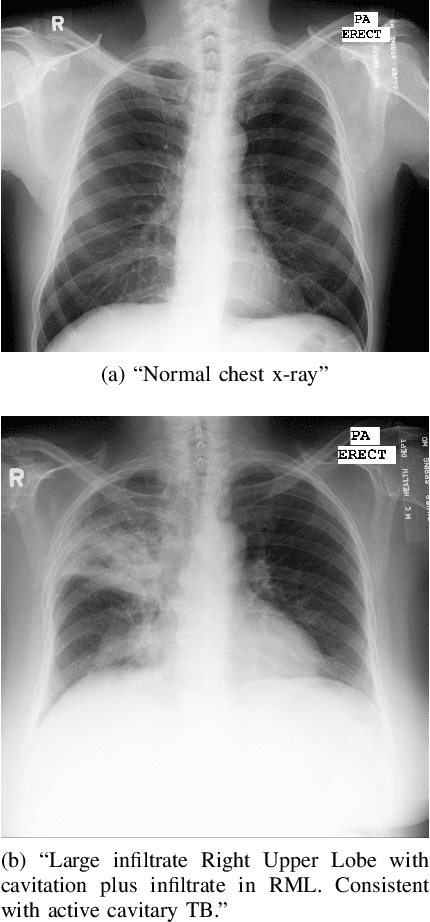

Abstract:Machine learning has significantly advanced healthcare by aiding in disease prevention and treatment identification. However, accessing patient data can be challenging due to privacy concerns and strict regulations. Generating synthetic, realistic data offers a potential solution for overcoming these limitations, and recent studies suggest that fine-tuning foundation models can produce such data effectively. In this study, we explore the potential of foundation models for generating realistic medical images, particularly chest x-rays, and assess how their performance improves with fine-tuning. We propose using a Latent Diffusion Model, starting with a pre-trained foundation model and refining it through various configurations. Additionally, we performed experiments with input from a medical professional to assess the realism of the images produced by each trained model.